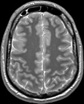

Visible Human male: Sectio transversalis 1056

CT

NMR

Pd T1 T2